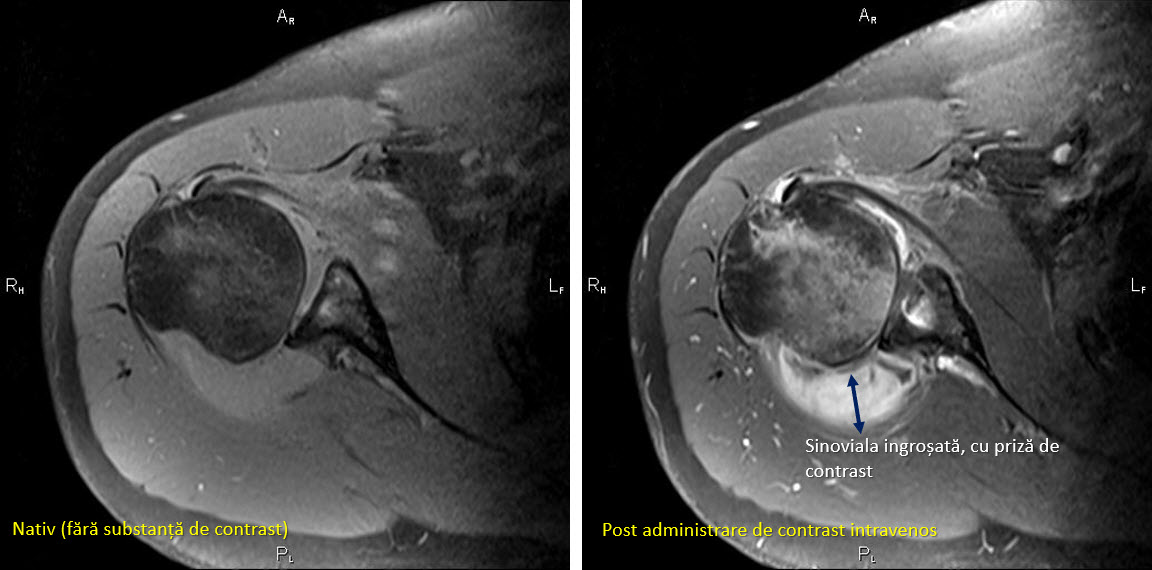

Există anumite suspiciuni de diagnostic pentru care este necesară administrarea de substanță de contrast (tumori, sinovite, alte patologii).

În cazuri atent selecționate poate fi necesară injectarea intraarticulară a substanței de contrast. Aceasta substanță de contrast va destinde toate recesurile articulației și va permite evidențierea leziunilor labrale, cartilaginoase sau anumite leziuni specifice cum ar fi leziunea capului lung al bicepsului de tip SLAP. Injectarea substanței de contrast se face de obicei prin abord posterior, sub ghidaj ecografic și secvențele dedicate artrografiei sunt diferite de cele dintr-o examinare prin rezonanță magnetică uzuală.

De obicei examinarea artro-rezonanță magnetică aduce informații suplimentare în cazuri selectate, după ce pacienții au avut mai întâi examinarea prin rezonanță magnetică nativă și aceasta nu a fost concludentă. Rar, atunci când mecanismul traumatismului este înalt sugestiv pentru o leziune potențial vizibilă doar pe artro-rezonanță magnetică, se efectuează artro-rezonanță magnetică fără examinarea nativă în prealabil. Chiar și în acest caz este nevoie să efectuăm câteva secvențe specifice examinării native (cel puțin un STIR/ PD cu fatsat și cel puțin o secvența T1 fără fatsat) - în caz contrar, anumite patologii acute, cum ar fi contuziile osoase sau fracturile oculte ar putea rămâne inaparente.